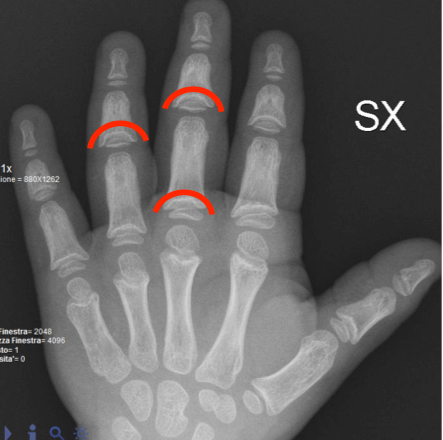

Nel sospetto di displasia scheletrica sono stati eseguiti cariotipo e analisi del gene SHOX risultati nella norma, e acquisiti radiogrammi total-body, da cui sono emersi due elementi guida: l’aspetto di deformazione conica delle falangi intermedie e prossimali (cone-shaped epiphyses) (Figura 1), associate a irregolarità metafisarie elettivamente localizzate alle ginocchia di entità lieve (aree radiopache, trabecolatura grossolana) progressivamente più evidenti nel corso degli anni. Tali caratteristiche radiologiche rappresentano aspetti altamente specifici di ipoplasia cartilagine-capelli (CHH) / osteocondrodisplasia metafisaria tipo McKusick: la diagnosi è stata poi confermata al sequenziamento del gene RMRP che ha rilevato una mutazione in doppia eterozigosi, di cui entrambi i genitori sono portatori sani.